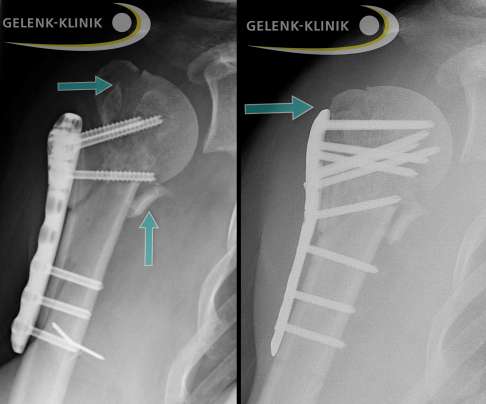

Vor allem bei Patienten mit Osteoporose können Implantate (Platten oder Schrauben), die der Operateur zur Stabilisierung des Bruchs eingebracht hat, versagen. Die Implantate können sich lockern oder brechen aus und die vorher fixierten Knochenfragmente verschieben sich erneut. Bei nur leichten Beschwerden reicht es teilweise aus, störendes Material zusammen mit Narbengewebe zu entfernen, um eine Linderung zu erzielen.

Nach der Behandlung können die Knochenfragmente abkippen oder sich verschieben

Auch nach ärztlicher Behandlung ist es möglich, dass sich die gebrochenen Knochenanteile des Oberarmkopfes erneut verschieben oder gegeneinander verdrehen (sekundäre Verschiebung). Die Ursache liegt oft darin, dass die Patienten das Schultergelenk zu früh belasten und der Bruch noch nicht vollständig verheilt ist. Eine bestehende Osteoporose begünstigt Abkippungen. Grund dafür ist, dass mögliche Schrauben im weichen Knochen nur wenig Halt finden. So besteht beispielsweise die Gefahr, dass das Kopffragment abrutscht oder das Tuberculum majus durch den Sehnenzug ausreißt.

Bleiben die Verschiebungen im Bereich weniger Millimeter, kann der Patient sie häufig noch tolerieren. Für größere Verschiebungen – gerade wenn sie zeitnah zum Unfall oder einer Operation auftreten – bietet sich die Möglichkeit einer operativen Korrektur.

Korrektur einer Fehlstellung nach operativer Stabilisierung des Bruchs

Nach einer Operation mit Stabilisierung der einzelnen Bruchfragmente durch Schrauben und Platten kann es im weiteren Verlauf zu einem Abrutschen des Bruchs kommen. Es bildet sich eine Fehlstellung. Eine erneute Operation kann diese korrigieren.

Eventuell zeigen die Röntgenaufnahmen instabile Knochenteile, sodass später doch operiert werden muss. In dem Fall erfolgt eine operative Fixierung und Ausrichtung mit Schrauben und Platten.